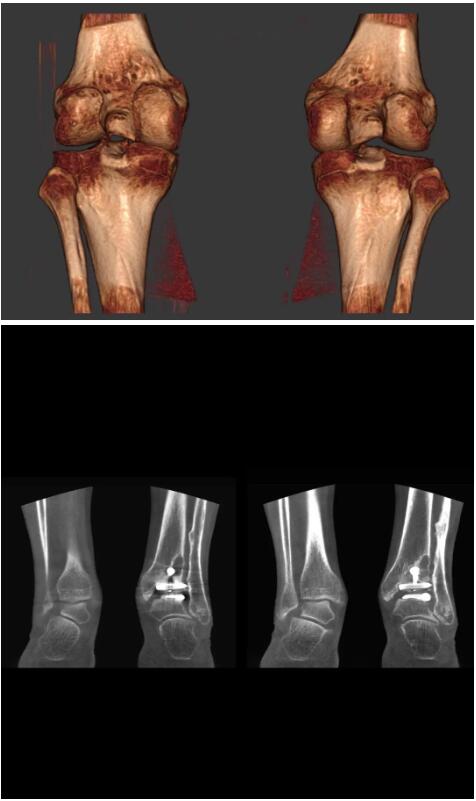

比如上面這款專用于足部和踝部掃查的CT成像系統(tǒng),患者在進(jìn)行CT掃查時只需要站在上面即可,雙腳站或者單腳站都可以,當(dāng)然,如果患者不是那么方便站著做完CT掃查,也可坐在上面。

這款CT掃查系統(tǒng)自帶屏蔽裝置,它的體積非常小,僅需要極小的空間即可,并不像常規(guī)CT那樣需要一間單獨的檢查室。此外,這種CT掃查的速度非???,僅需30秒左右可以完成檢查,輻射劑量相對常規(guī)的CT要少許多,尤其適合醫(yī)院的骨科使用。

而患者站著做足部或者踝部做CT檢查還有個好處是,可以檢查患者在負(fù)重的情況下,骨關(guān)節(jié)的真實情況,而躺著做CT掃查時未必能看出來。負(fù)重CT掃查特別是對于受傷的運動員或者舞蹈員來說意義更大,能夠更準(zhǔn)確地評估傷情,幫助他們盡早復(fù)原。

以下是這些“特立獨行”的CT所拍出來的圖像: